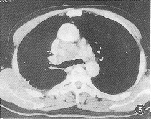

CT诊断纵隔受侵的标准包括肿瘤与纵隔相连、侵及血管或瘤体与纵隔结构间脂肪层消失等[3]。但有时从CT影像上不能区别炎性粘连和癌性浸润,对周围脂肪的早期浸润也有一定限度。动态增强扫描的应用可提高准确性,特别是当见到肿瘤包绕血管(图3)或明显浸润纵隔脂肪时,CT诊断相当可靠。文献报道CT诊断肿瘤侵犯纵隔、心脏及大血管的准确率为70%[3],本组资料为75%,与之相符。

图3 ⅢB(T4N1M0)肺癌,肿瘤包绕右肺动脉,上腔静脉受压变形 图4 ⅢA(T2N2M0)肺癌,气管分叉前一肿大淋巴结,短径1.5 cm,病理证实为肺癌淋巴结转移 图5 纵隔内淋巴结肿大融合成团